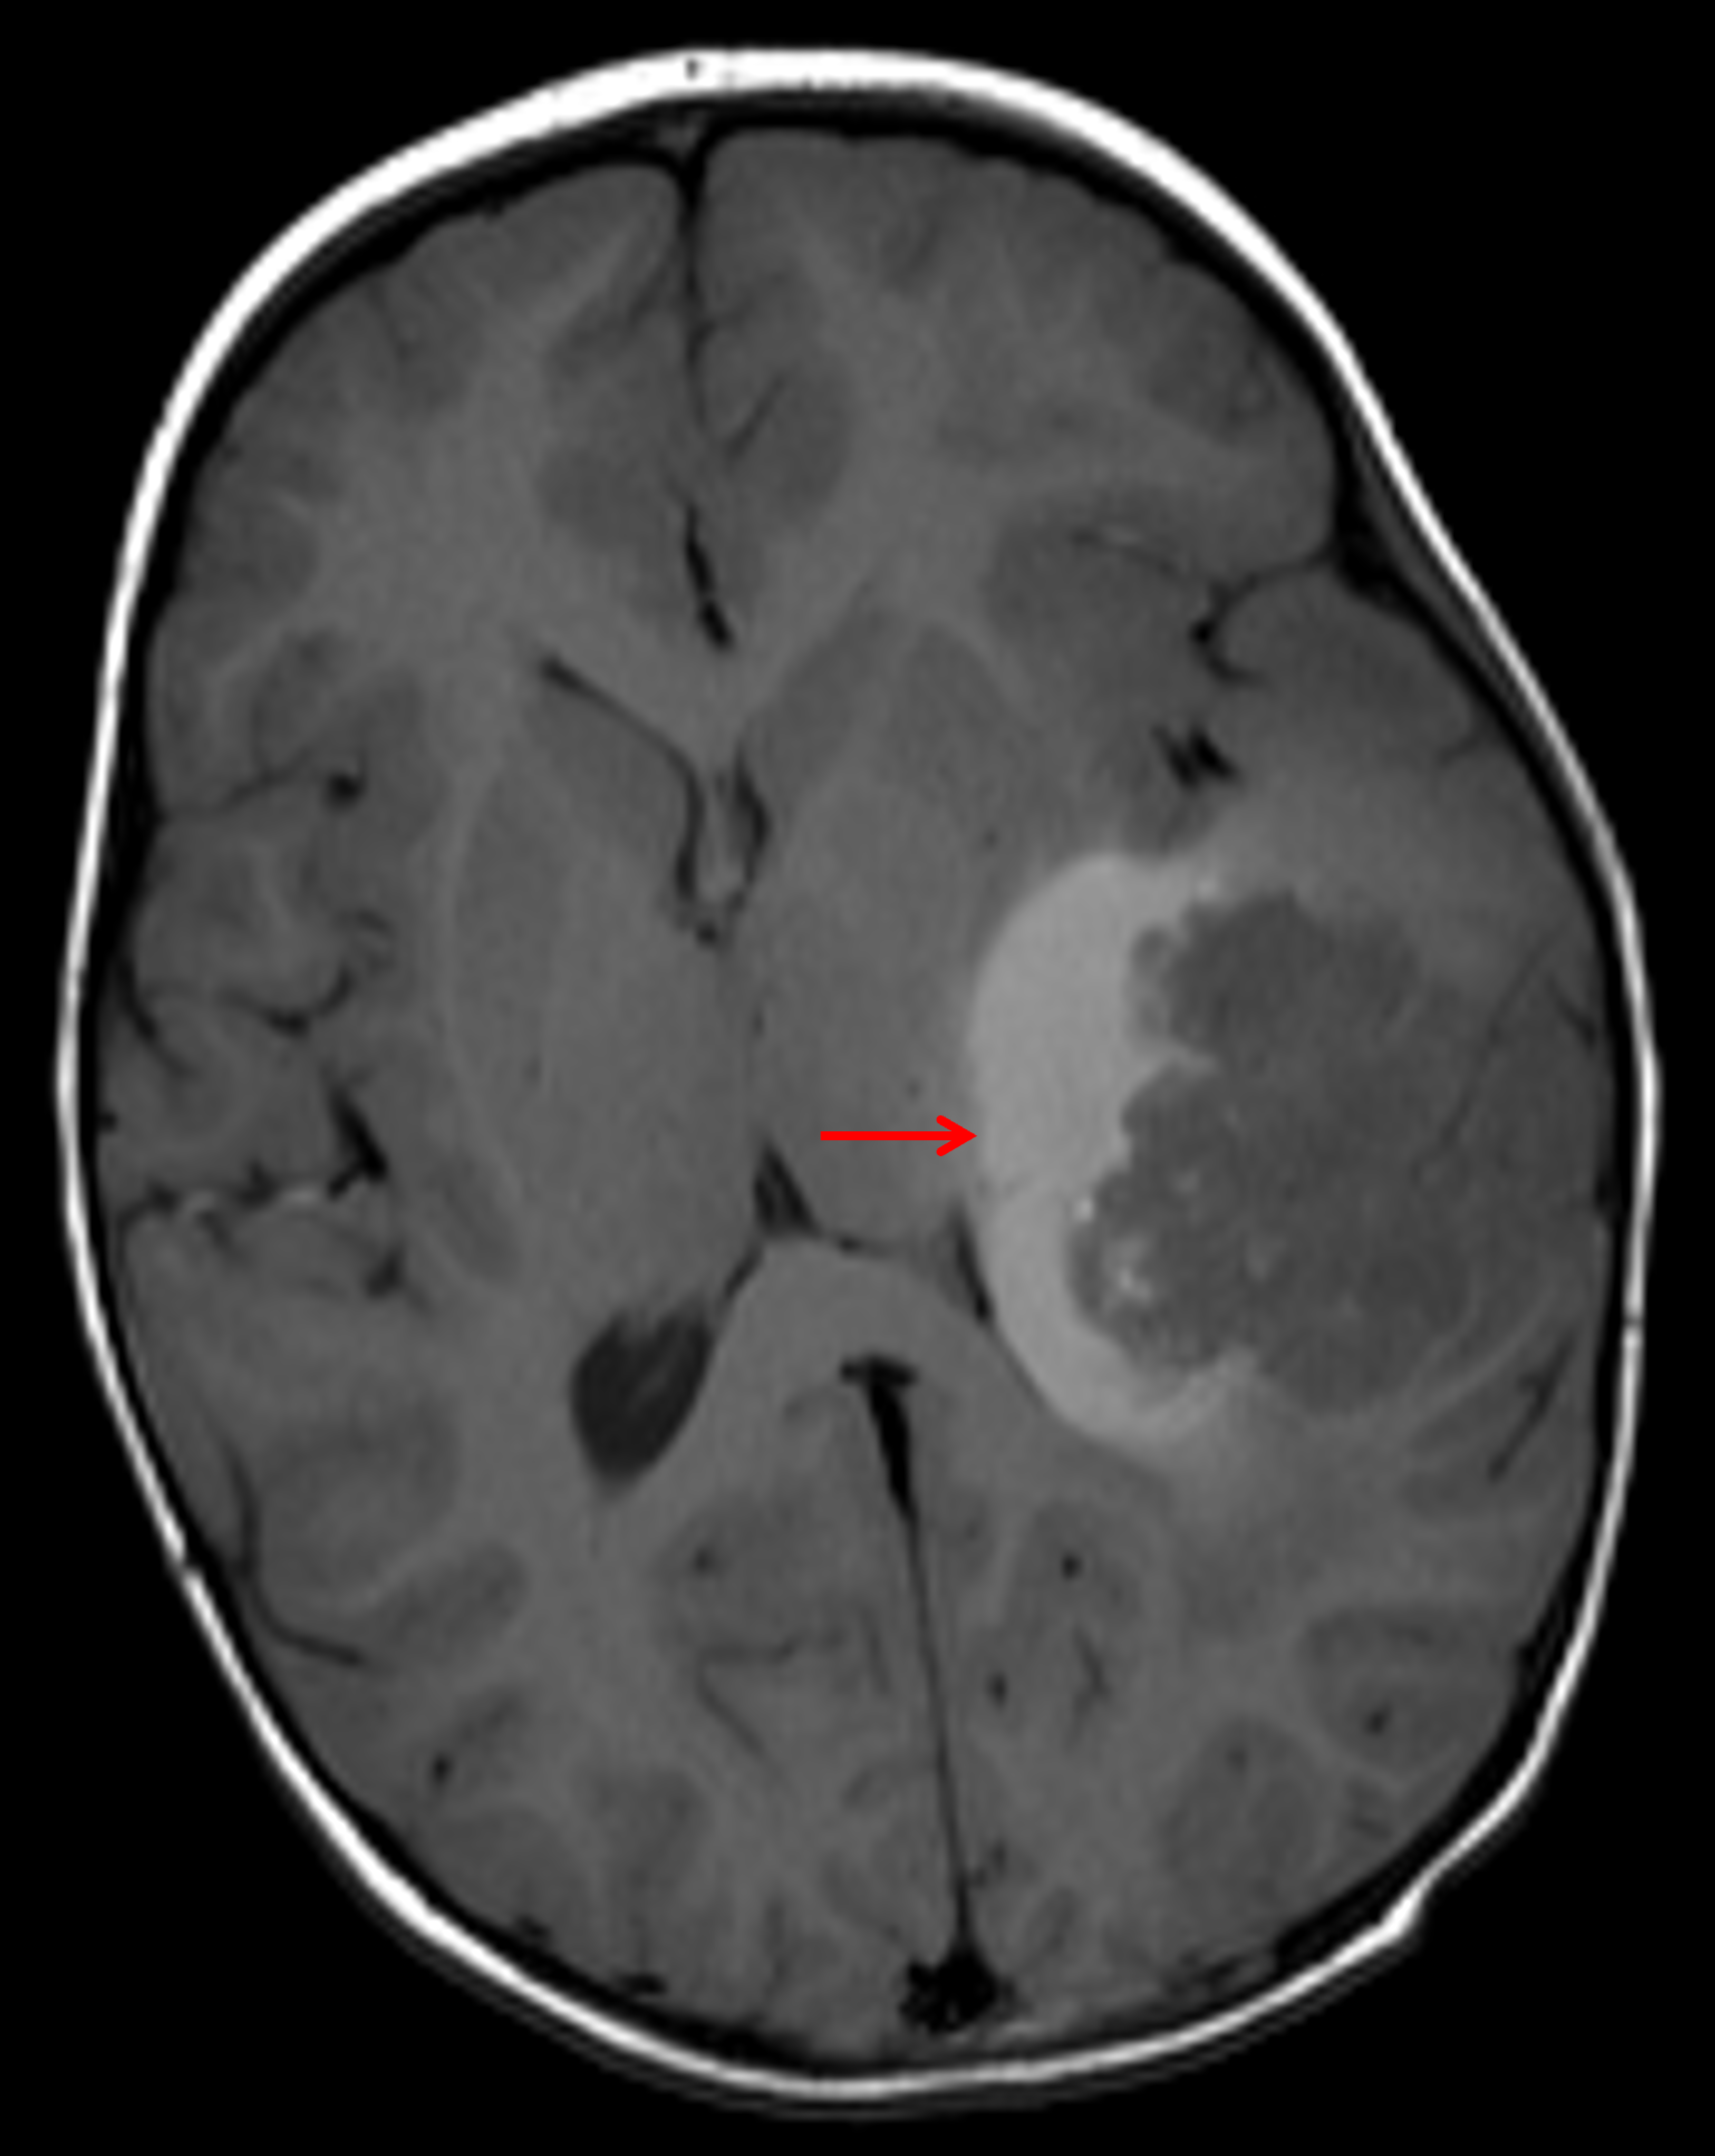

Age: 3

Sex: Male

Indication: Speaking difficulty, imbalance

Atypical teratoid/rhabdoid tumor (AT/RT)